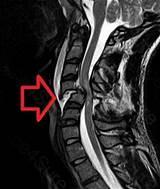

A patient with a spinal cord injury at T7 tells the nurse that they now...

A patient with a spinal cord injury at T7 tells the nurse that they now have a pounding headache. The nurse should

check for bladder distension.